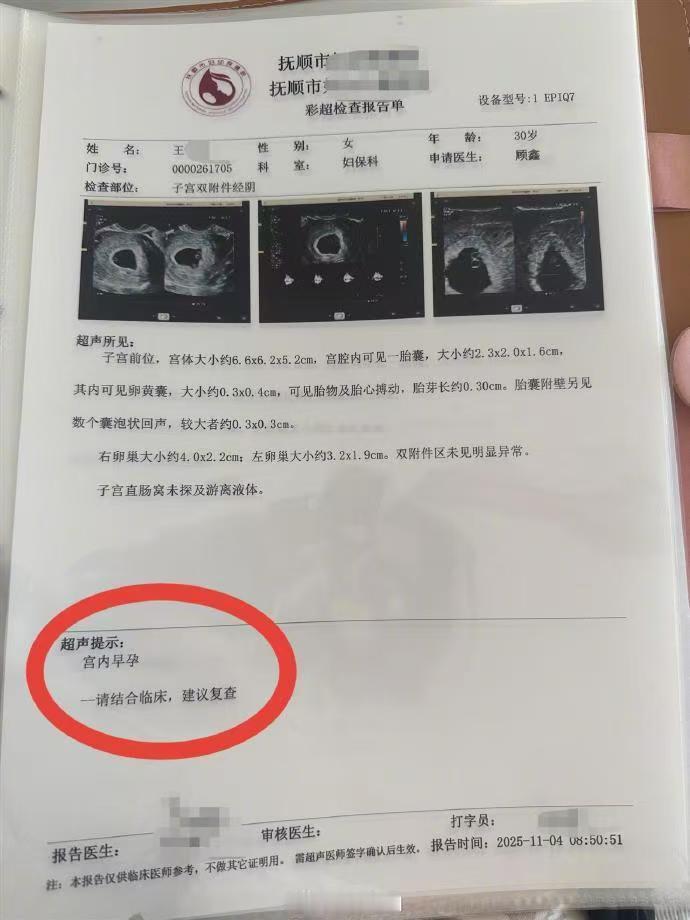

辽宁抚顺的一位准妈妈最近经历了人生中过山车般的时刻。怀孕16周的王女士,原本只是按部就班地进行产检,却在医院拿到了一份极其罕见的诊断报告。从去年11月到12月,短短一个月的时间里,她在医院进行了四次产检,每一次彩超单上的图像都在发生变化——最终确认,她怀上了四胞胎。 这并非普通的四胞胎。根据相关医生的诊断,王女士怀上的是同卵四胞胎。在医学领域,同卵四胞胎的发生率极低,属于非常罕见的个案。更复杂的情况在于,医生指出第四个胎儿为“无心畸胎”。这是一个专业性很强的术语,意味着这个胎儿虽然没有正常的心脏发育,但依然依赖其他胎儿的血液循环在母体内生存。这种特殊的医学状况,无疑给整个孕期增添了巨大的不确定性和风险。 对于普通家庭而言,多胞胎往往意味着双倍的喜悦,但在医学视角下,这更多代表着高风险妊娠。从数据来看,自然受孕情况下同卵四胞胎本就凤毛麟角,而伴随无心畸胎的情况更是让保胎之路布满荆棘。王女士在抚顺当地医院进行的这四次检查,实际上是一个不断排查和确认的过程。每一次彩超,不仅是在数胎儿的数量,更是在评估母体和每一个胎儿的生存质量。 网友们对此议论纷纷,有人感叹生命的奇妙与不易,也有人为即将到来的抚养压力感到担忧。毕竟,四个孩子的降生,对家庭的经济状况、父母的精力都是极大的考验。目前摆在王女士和家人面前的,不仅是喜悦,还有如何根据医生的专业建议,制定最科学、最安全的后续妊娠方案。 这起事件也给广大备孕及孕期女性提了个醒:规范的产检流程至关重要。像王女士这样,通过连续、定期的超声检查,才能及时发现多胎妊娠及胎儿发育异常等特殊情况。面对罕见病例,医学干预和监测是保障母婴安全的最有效手段。祝愿这位准妈妈能平安度过接下来的孕期,也希望这个小生命群体能在现代医学的保驾护航下,迎来最好的结局。 以上内容仅供参考和借鉴